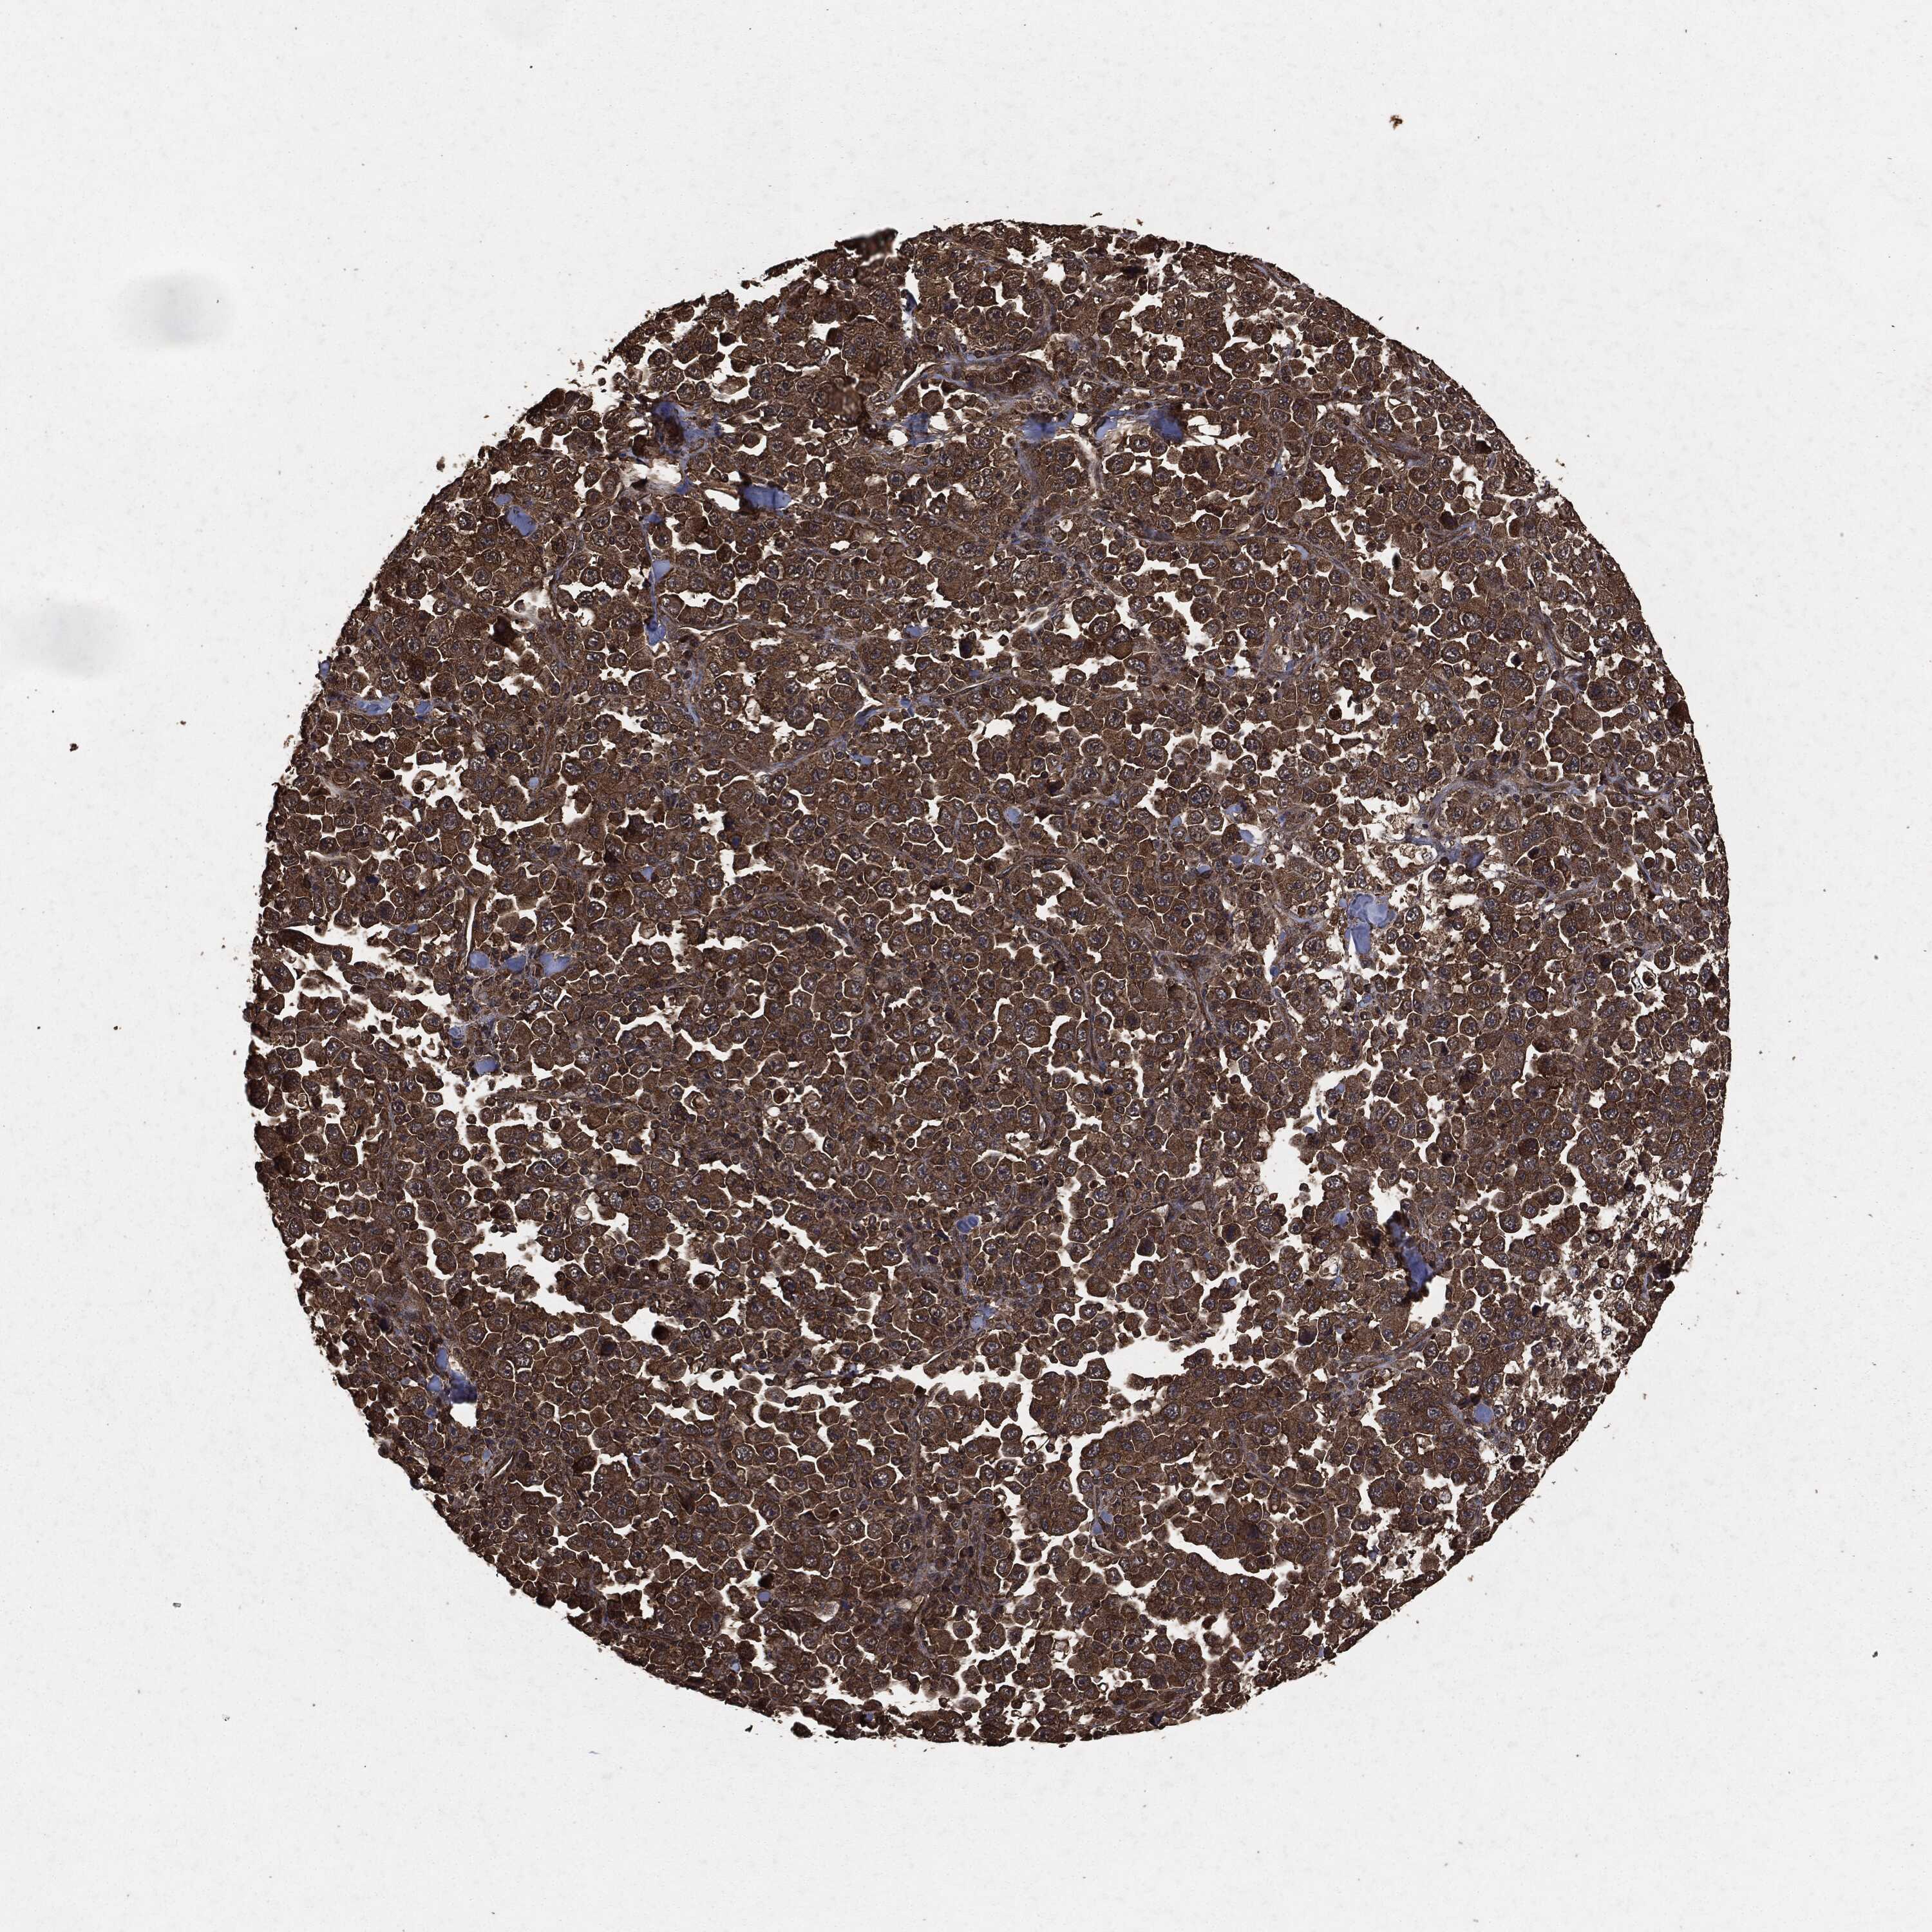

STOMACH CANCER - Protein expressioni

A mouse-over function shows sample information and annotation data. Click on an image to view it in a full screen mode. Samples can be filtered based on level of antibody staining by selecting one or several of the following categories: high, medium, low and not detected. The assay and annotation is described here.

Note that samples used for immunohistochemistry by the Human Protein Atlas do not correspond to samples in the TCGA dataset.

Antibody stainingi

Antibody staining in the annotated cell types in the current human tissue is reported as not detected, low, medium, or high, based on conventional immunohistochemistry profiling in selected tissues. This score is based on the combination of the staining intensity and fraction of stained cells.

Each image is clickable and will lead to virtual microscopy that enables deeper exploration of all samples and also displays staining intensity scores, fraction scores and subcellular localization as well as patient and tissue information for each sample.

HPA049830

CAB002015

CAB080330

CAB080331

CAB080332

Staining

High

Medium

Low

Not detected

Intensity

Strong

Moderate

Weak

Negative

Quantity

>75%

75%-25%

<25%

None

Location

Nuclear

Cytoplasmic/membranous

Cytoplasmic/membranous,nuclear

Adenocarcinoma, NOS

Adenocarcinoma, High grade